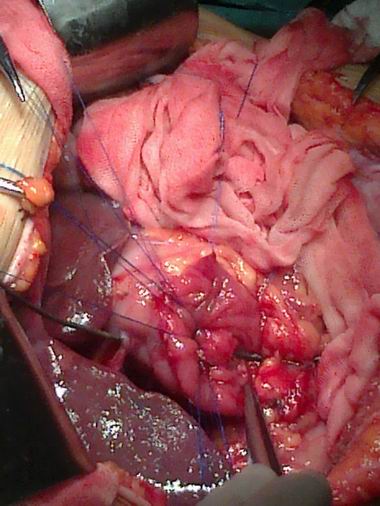

海医附院普通外科成功实施腹腔镜近端胃癌根治术

海医附院普通外科成功实施腹腔镜近端胃癌根治术 发布时间:2012-7-12 被阅览数: 223 次 海医附院普外科 海医附院普外科不断提升打造新技术开展的能力,充分调动各专业医生的积极性, 海医附院普外科 海医附院普外科...